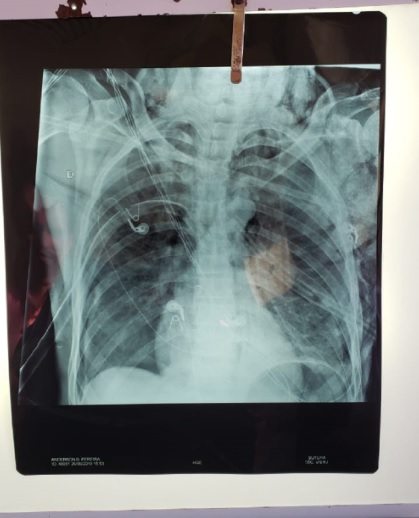

Um homem de 41 anos foi atingido por flecha, na tarde desta quinta-feira (26), e teve os dois pulmões perfurados no bairro da Federação, em Salvador. Segundo o jornal Correio, a vítima identificada como Anderson Cleiton Batista Pereira chegou ao Hospital Geral do Estado (HGE) inconsciente, com o objeto atravessado no corpo.

A cirurgia para a retirada do objeto durou quase 10 horas, sendo concluída apenas no início da madrugada desta sexta-feira (27), quando ele foi encaminhado para a Unidade de Terapia Intensiva (UTI), onde permanece internado em estado considerado grave.